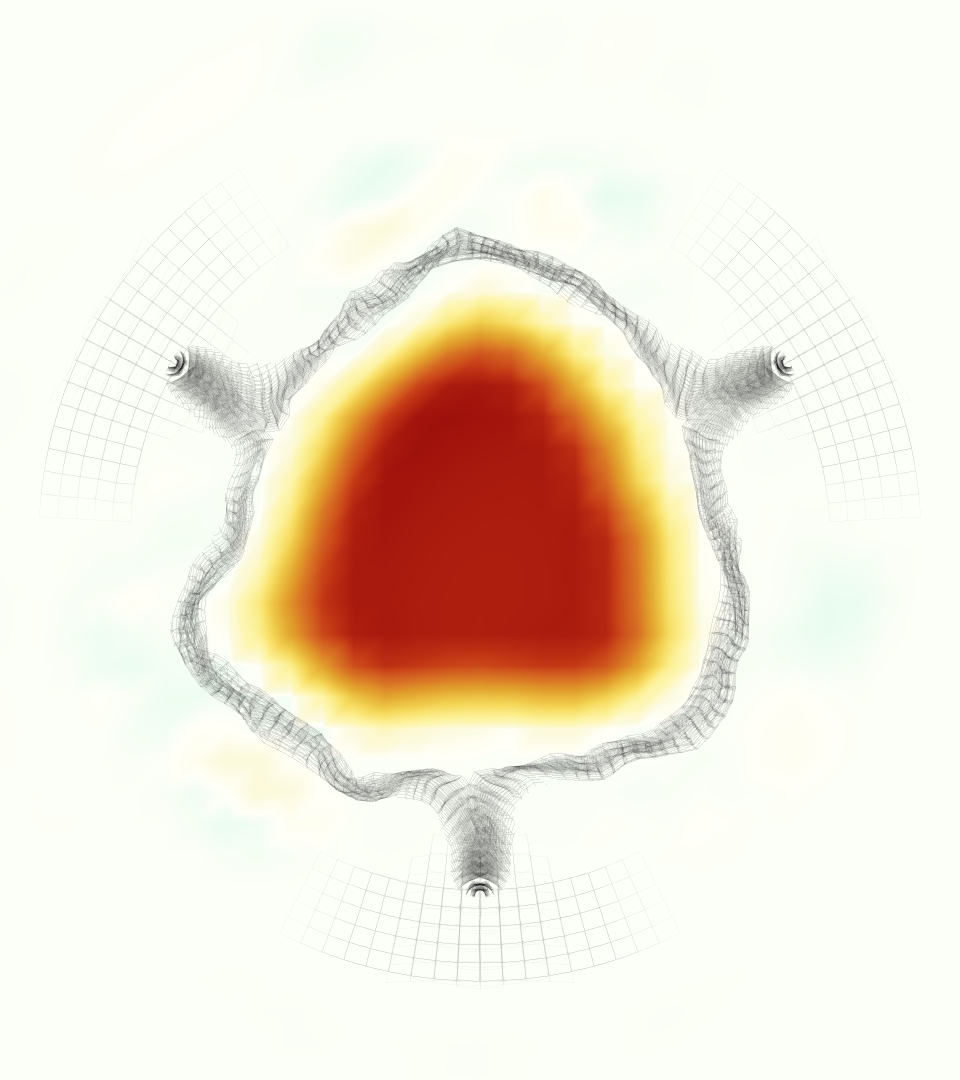

At = 0, the axial slice directly at the valve annulus shown in columns 1 and 2 in Figure 6, there was excellent agreement between the simulation and experiment over the cardiac cycle in the speed and shape of the jet through the valve. In both cases, the axial velocity increased as the flow accelerated during systole and the valve leaflets opened, then decreased during diastole with slight negative velocity before the valve leaflets were fully closed. The forward flow through the valve annulus did not form a full circle, but rather developed a triangular shape with a point of the triangle forming along the interior curve of the vessel, at the bottom of the axial slices. At = 0, the points of this triangular jet shape aligned with the commissures of the valve. This shape persisted during peak systole and was well-matched by the simulation.

The axial slice = 0.625 cm, shown in columns 3 and 4 in Figure 6, cut through the support scaffolding of the valve and the leaflets when they are open. In the experimental data, the shape of the jet changed as it moved downstream. A triangular shape occurred, but the points were then aligned with the middle of each open leaflet as opposed to the commissures. Those points were also more rounded than they were at = 0. The peak velocity of the jet was faster at = 0.625 cm than at = 0, as the flow accelerated through the open valve leaflets. The simulation produced these features at = 0.625 cm. The triangular shape of the jet shifted similarly, and its speed increased compared to the upstream slice. As the flow decelerated into diastole, the jet shape remained roughly triangular but diminished in intensity before disappearing after valve closure.

The jet continued to develop at = 1.25 cm, an axial slice immediately downstream of the valve scaffolding and open leaflets, shown in columns 5 and 6 in Figure 6. In the experimental data, the points of the triangular jet shape extended further towards the vessel wall. In addition, regions of reversed flow developed in the locations downstream of the commissures, resulting in curved sides to the shape of the jet. Each tip of the jet was unique, due to variations in the individual leaflets in the physical bioprosthetic valve. These variations are apparent in the velocity fields, possibly because the jet edges are similar enough cycle to cycle that irregularities are still being captured even with phase averaging. Further discussion of these features can be found in Schiavone et al. [39], which showed that the jet tip shapes occurred in different pulmonary anatomies, demonstrating that they were likely due to inherent properties of each leaflet. The leaflets in the mathematical model of the valve are identical, so these nuances in leaflet variation could not be replicated. The simulation did capture some of the extension of the tips of the jet, as they were closer to vessel wall at slice = 1.25 cm than = 0.625 cm. The curves in the triangular sides of the jet were also present in the simulation, though they were less pronounced than the experimental data. At both = 0.625 cm and = 1.25 cm, the jet shape in the simulation was smoother than the jet in experiment. It is possible that the free edges of the leaflets in the mathematical model are not fully replicating the behavior of the physical leaflets of the bioprosthetic valve, in particular the amplitude or frequency of leaflet flutter, leading to the variations seen in the jet shape at = 1.25 cm downstream of the leaflet edges. The simulation, however, does capture the key features of the triangular shape and speed of the jet. Overall, qualitative comparisons demonstrated that the simulation reproduced key features of the flow during systole and diastole.